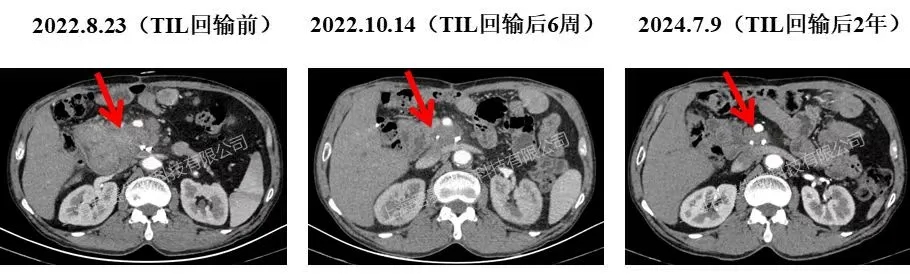

案例1(晚期胰腺癌):一例晚期胰腺癌患者,术后肿瘤复发伴肝内转移,入组接受GC101治疗。单次回输6周后,胰头10cm复发病灶缩至3cm,肝转移灶完全消失,肿瘤标志物恢复正常;后续复查病灶缩至1cm左右(钙化斑,无代谢活性),目前已恢复正常生活超39个月。

▲图源“JUNCELL”,版权归原作者所有,如无意中侵犯了知识产权,请联系我们删除